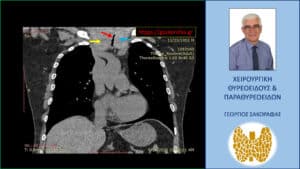

Αξονική τομογραφία – κατά μέτωπο διατομή σε άλλο επίπεδο. Απεικονίζεται η σημαντικού βαθμού στένωση της τραχείας (κόκκινο βέλος) από τον λίαν διογκωμένο δεξιό λοβό (κίτρινο βέλος) και τον διογκωμένο αριστερό λοβό (μπλε βέλος)